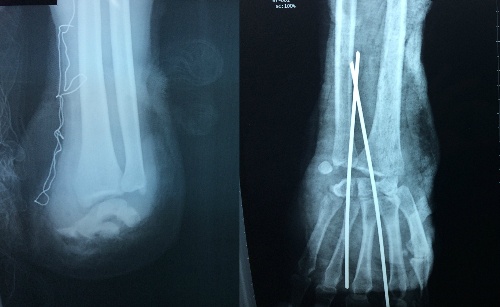

| Hình chụp X-quang cho thấy tay trái bệnh nhân bị đứt lìa, tay phải đứt cơ. Ảnh: Hòa Khánh. |